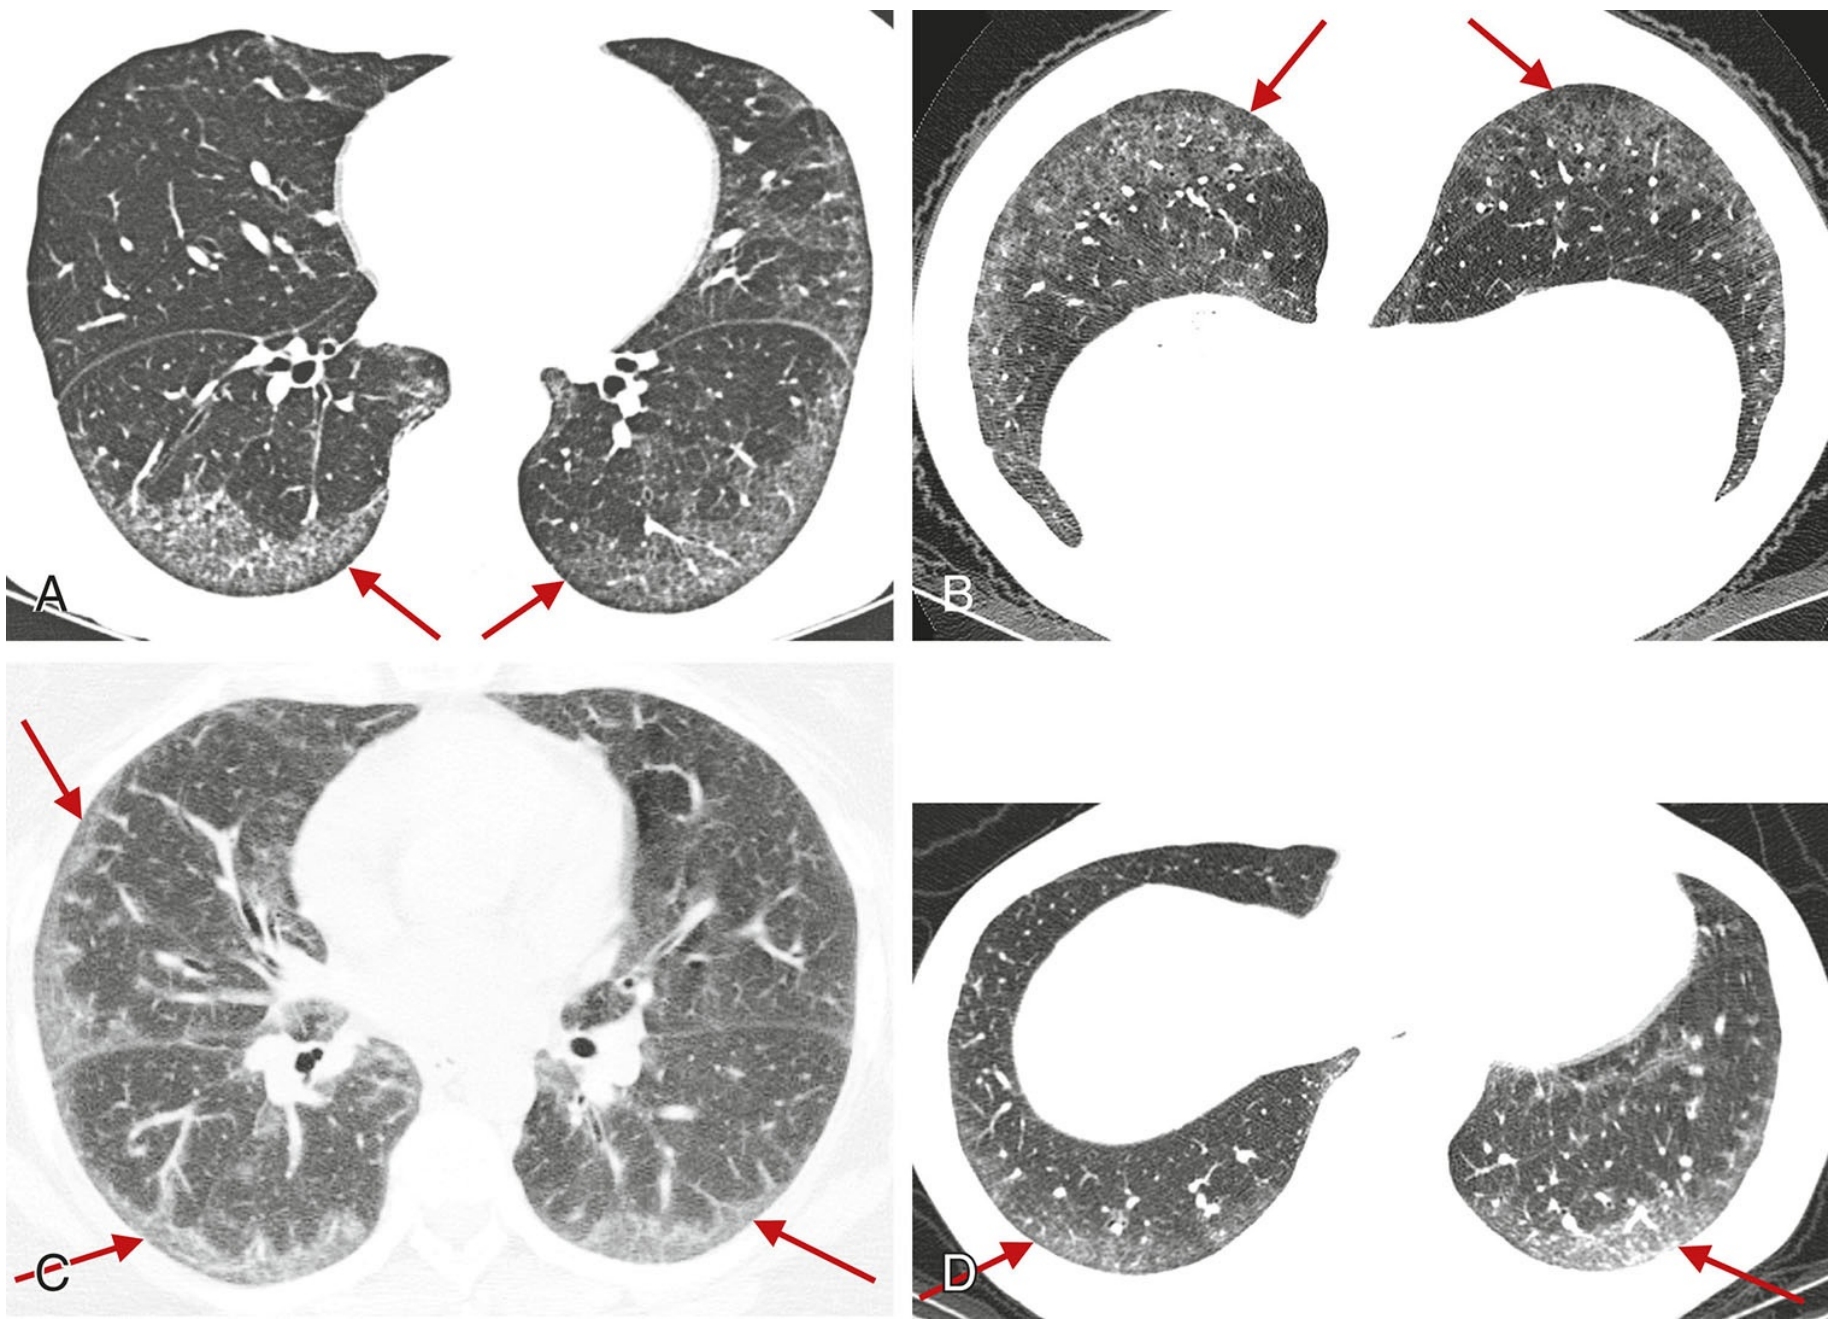

1b4163a751fee4c845315e379d18df02.png

低置信度诊断为UIP。

过敏性肺炎患者,俯卧位HRCT显示肺纤维化不以胸膜下分布为主(A), 且不累及肋膈角(B)。由于病灶以肺中央及上肺分布为主, 故与UIP表现不一致。

5e482130d89f117e603bc98d8f99b113.png

结节病患者,HRCT显示大片纤维化实变和组织结构变形,呈支气管血管周围分布。由于病变分布于肺中央和肺上叶,因此HRCT表现与UIP相悖。

dcc73822c0d09680dcf2fa4acce54499.png

A.过敏性肺炎患者,HRCT显示中肺分布为主的广泛蜂窝征;

B.呼气相,肺底层面,显示双肺散在的空气潴留(箭)。虽然存在蜂窝征,HRCT并不提示诊断UIP。由于存在中肺分布和空气渚留,此例被认为与UIP表现相悖。